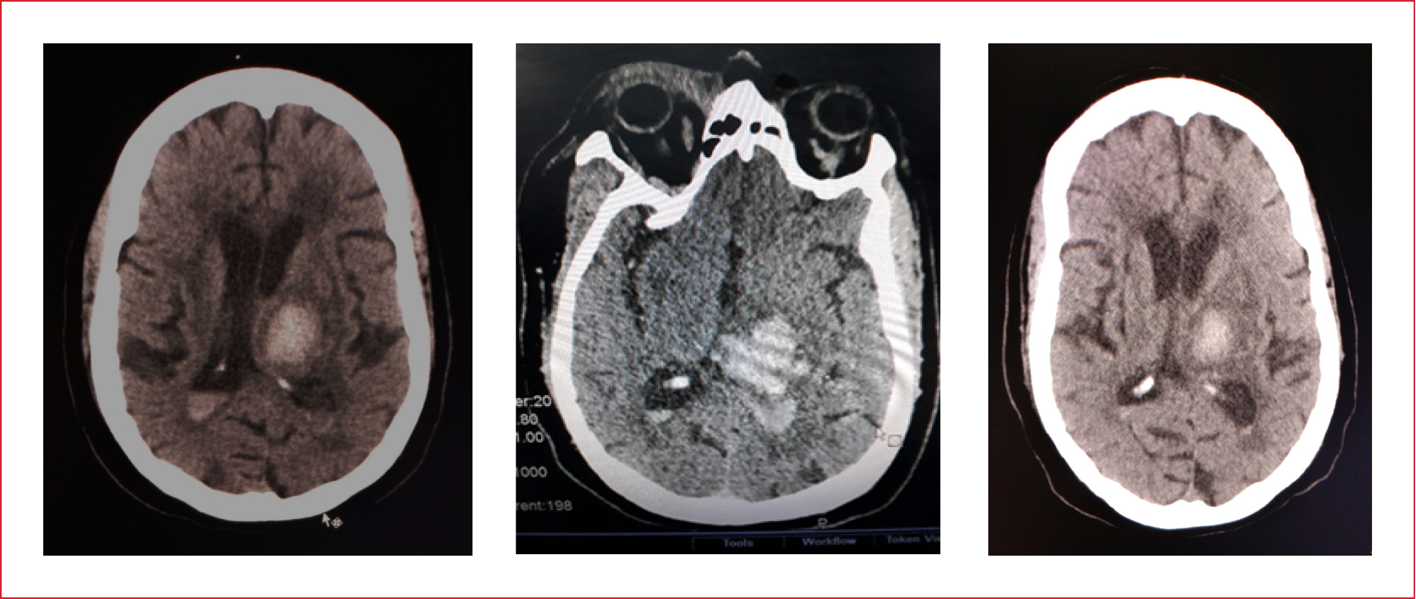

En la TC de cráneo (simple), se detectó una hemorragia intracraneal, de posible origen en el tálamo izquierdo, con extravasación en el ventrículo lateral izquierdo (Figura 1).

Figura 1. Tomografía computarizada de cráneo.

Hemorragia intraparenquimatosa talámica izquierda abierta al sistema

ventricular.

El diagnóstico de ingreso fue HIC espontánea no traumática, talámica izquierda con extravasación en el ventrículo lateral izquierdo y broncoaspiración de contenido gástrico (posible).

La TC de cráneo reveló una hemorragia talámica izquierda, sin edema cerebral y extravasación de sangre en los cuernos posteriores de los ventrículos, más en el izquierdo.